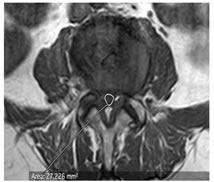

CASE 1

LUMBARIZED S1 VERTEBRA IS NOTED

T1W PARASAGITTAL IMAGE SHOWING MODERATE THECAL SAC STENOSIS ON THE LEFT (OBLITERATION OF FAT PLANE) ABUTTING THE L5 EXITING NERVE ROOT AT L5-S1 LEVEL

T1W AXIAL IMAGE SHOWING SEVERE THECAL SAC STENOSIS (<75 mm2) AT L5-S1 LEVEL DUE TO DIFFUSE DISC BULGE AND LIGAEMETNUM FLAVUM HYPERTROPHY AND FACETAL ARTHROPATHY